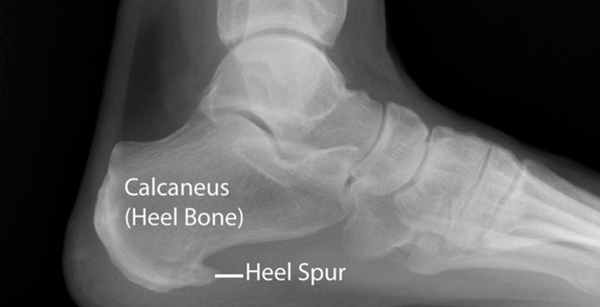

Пяточная шпора представляет собой остеофит пяточной кости. Этиологией шпор является наследственность, нарушения обмена веществ, туберкулез, ревматоидный артрит и системные воспалительные заболевания. К буграм пяточной кости прикрепляется множество мышц и подошвенная фасция, которые оказывают тракционное усилие на кость. Если пяточная шпора располагается на задней поверхности пяточной кости, то это дорсальная пяточная шпора, если она находится по подошвенной поверхности, то это подошвенная пяточная шпора. Дорсальные шпоры часто ассоциируются с тендинопатией ахиллова сухожилия, в то время как подошвенная шпора связана с подошвенным фасциитом. Вершина шпоры находится либо в месте прикрепления фасции на медиальном бугорке пяточной кости, либо в месте прикрепления мышцы короткого сгибателя пальца. Подошвенная фасция во время ходьбы претерпевает постоянное растяжение в связи с ритмичным опусканием и подъемом свода стопы, что приводит к хроническому растяжению апоневроза, которое предрасполагает к воспалительной реакции. Пронация стопы вызывает асимметричное натяжение подошвенной фасции. Избыточная пронация приводит к увеличению натяжения подошвенного апоневроза в месте прикрепления к бугру пяточной кости и считается основным механическим фактором развития подошвенной пяточной шпоры. Хроническая микротравма, которая вызывает разрывы подошвенной фасции вблизи ее прикрепления к кости, приводит к воспалению с дальнейшим развитием оссификации. Пяточная шпора прогрессирует в связи с длительным давлением на подошвенную фасцию и мышцы стопы, или растяжением подошвенной фасции вследствие избыточной подвижности 1 луча. Гиперподвижность структур медиального края стопы дает неравномерность натяжения подошвенной фасции. В области прикрепления фасции к пяточному бугру развивается хроническая микротравма и очаг воспаления, что приводит к развитию фасциита. По мере того, как воспалительный процесс приобретает черты хронического, развивается фиброз и оссификация в области пяточного бугра. Пяточная шпора может протекать либо бессимптомно, либо вызывать боль. Бессимптомные пяточные шпоры встречаются среди нормального взрослого населения в 11% случаев. Большинство пациентов с болью в пятке- это взрослые среднего возраста. У человека под пяткой появляется болезненный участок. Боль, которая локализуется в области медиального бугорка пяточной кости, вызвана давлением на подошву стопы в области прикрепления подошвенного апоневроза к пяточной кости.

Рис. 7. Рентгенограмма стоп. Пяточная шпора